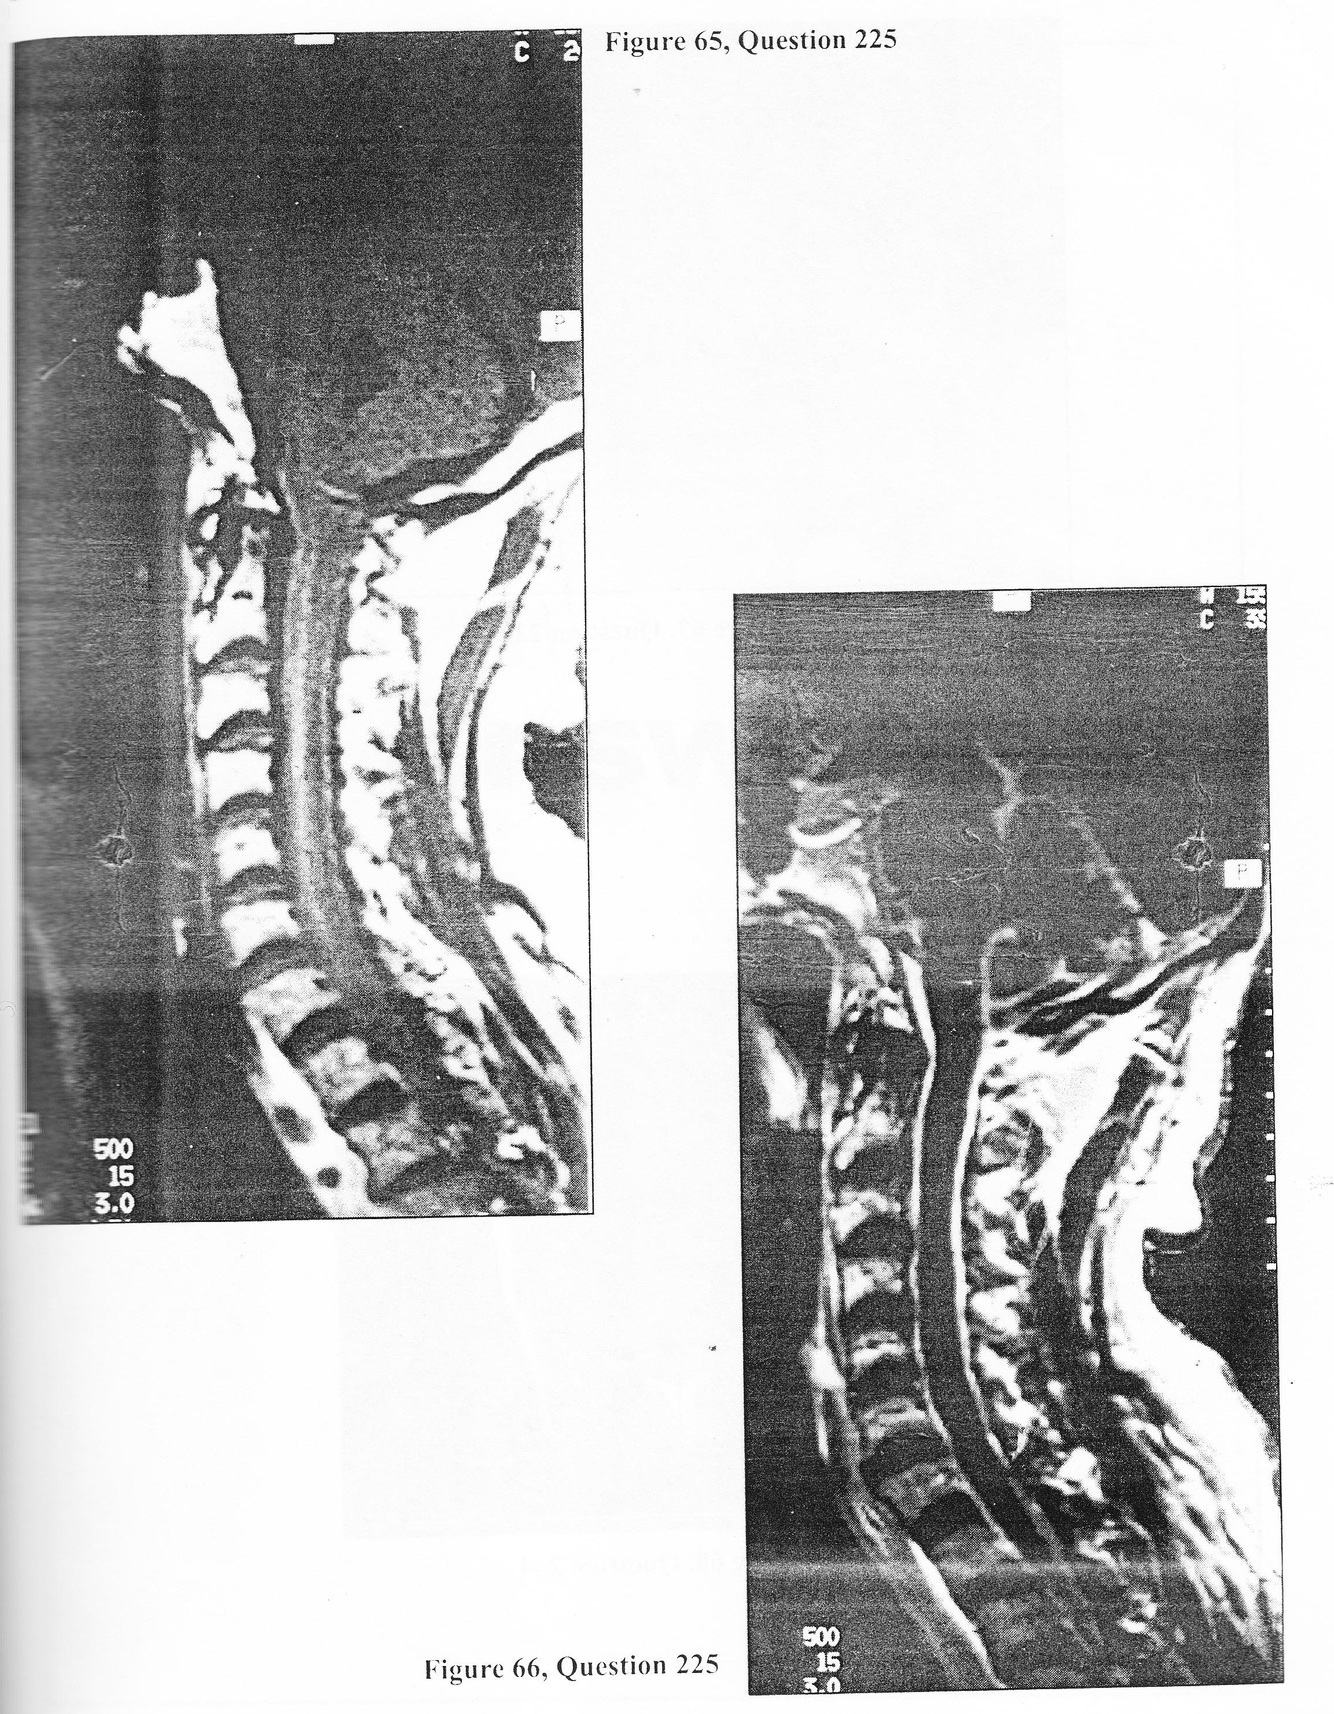

A 64-year-old Native American presents to a regional medical center in the southwestern United States with the progressive onset of fever, stiff neck, and quadriparesis. Unenhanced and enhanced Tl-weighted MRI images are represented by Figures 65 and 66. 225. Likely diagnoses for this patient include all of the following EXCEPT:

D. cysticercosis

A 64-year-old Native American presents to a regional medical center in the southwestern United States with the progressive onset of fever, stiff neck, and quadriparesis. Unenhanced and enhanced Tl-weighted MRI images are represented by Figures 65 and 66.

E. cervical and thoracic myelography